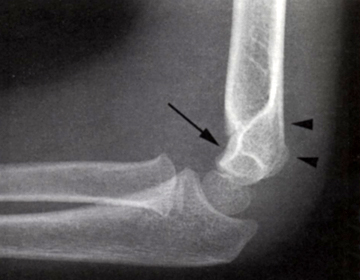

Se efter ”fad pad sign” som udtryk for ledansamling.

Manglende ansamling udelukker ikke fraktur.

En linie gennem centrum af radius skal altid gå lige igennem capitulum humeri.

En linie langs forsiden af humerus går normalt igennem midterste 1/3 del af capitulum humeri, hvis capitulum ligger bagved skal der reponeres og osteosynteres i GA. Hos børn under 4 år tillades lidt større dislokation.

Gartland type I Udisloceret men ansamling. Gips i 3 uger